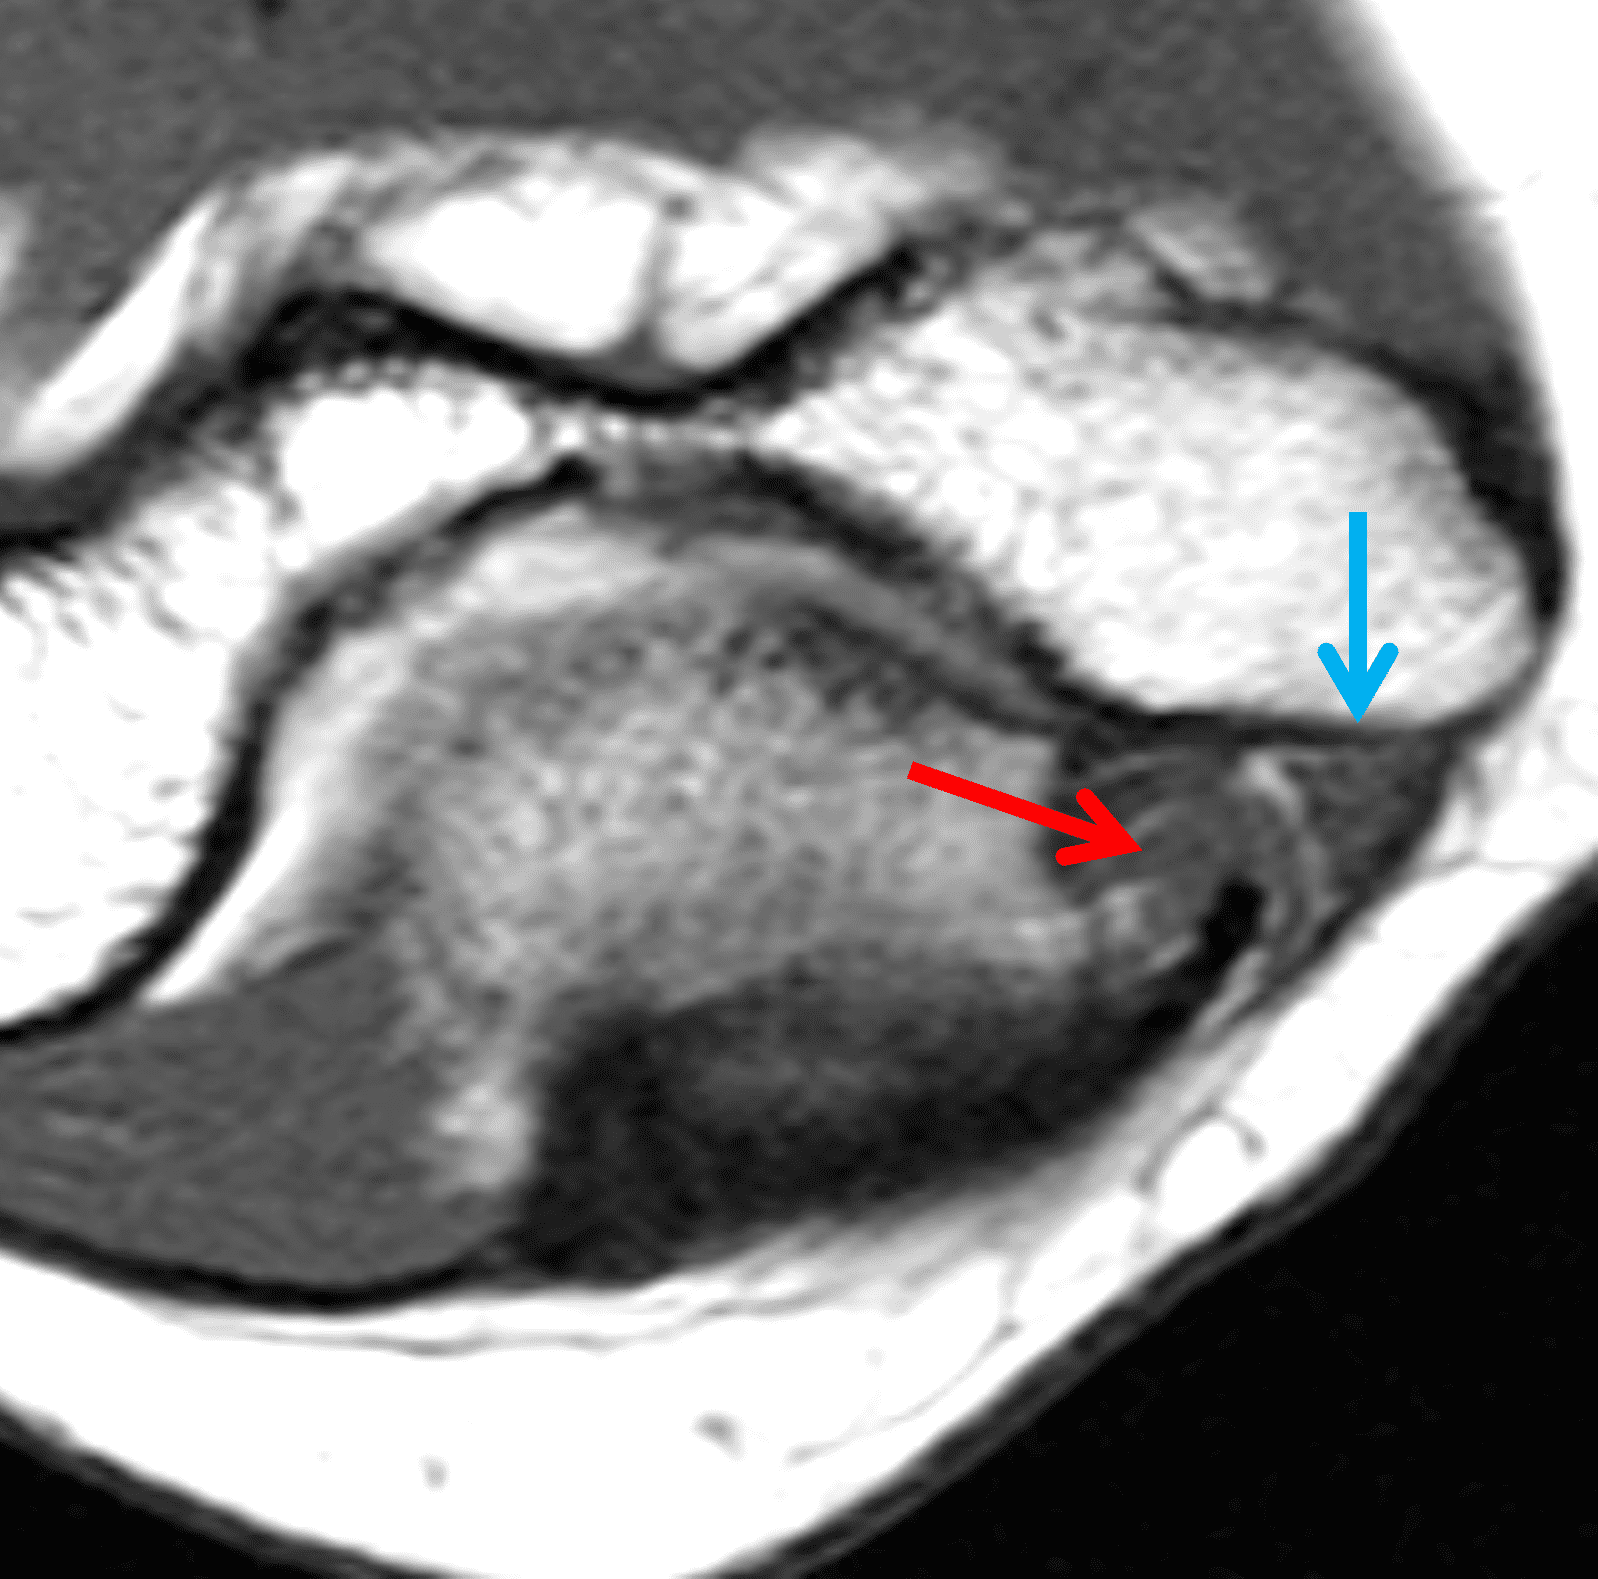

Figure 6: Cubital tunnel syndrome associated with an anomalous insertion of the medial head of the triceps. Axial (6A) T1-weighted and (6B) T2-weighted images at the level of the cubital tunnel retinaculum show the distal muscle belly and low signal-intensity tendon of the medial triceps (red arrows) filling more than half of the cubital tunnel cross-section. The ulnar nerve (blue arrows) is displaced by the muscle and appears compressed. This patient did not have any snapping or evidence of nerve subluxation with elbow flexion.